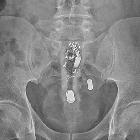

rektal eingeführter Vibrator

Radiographic features

In almost all cases plain radiography suffices and poses a little diagnostic difficulty. Occasionally body packers (drug smuggling) or some softer silicone objects may be less radiopaque.